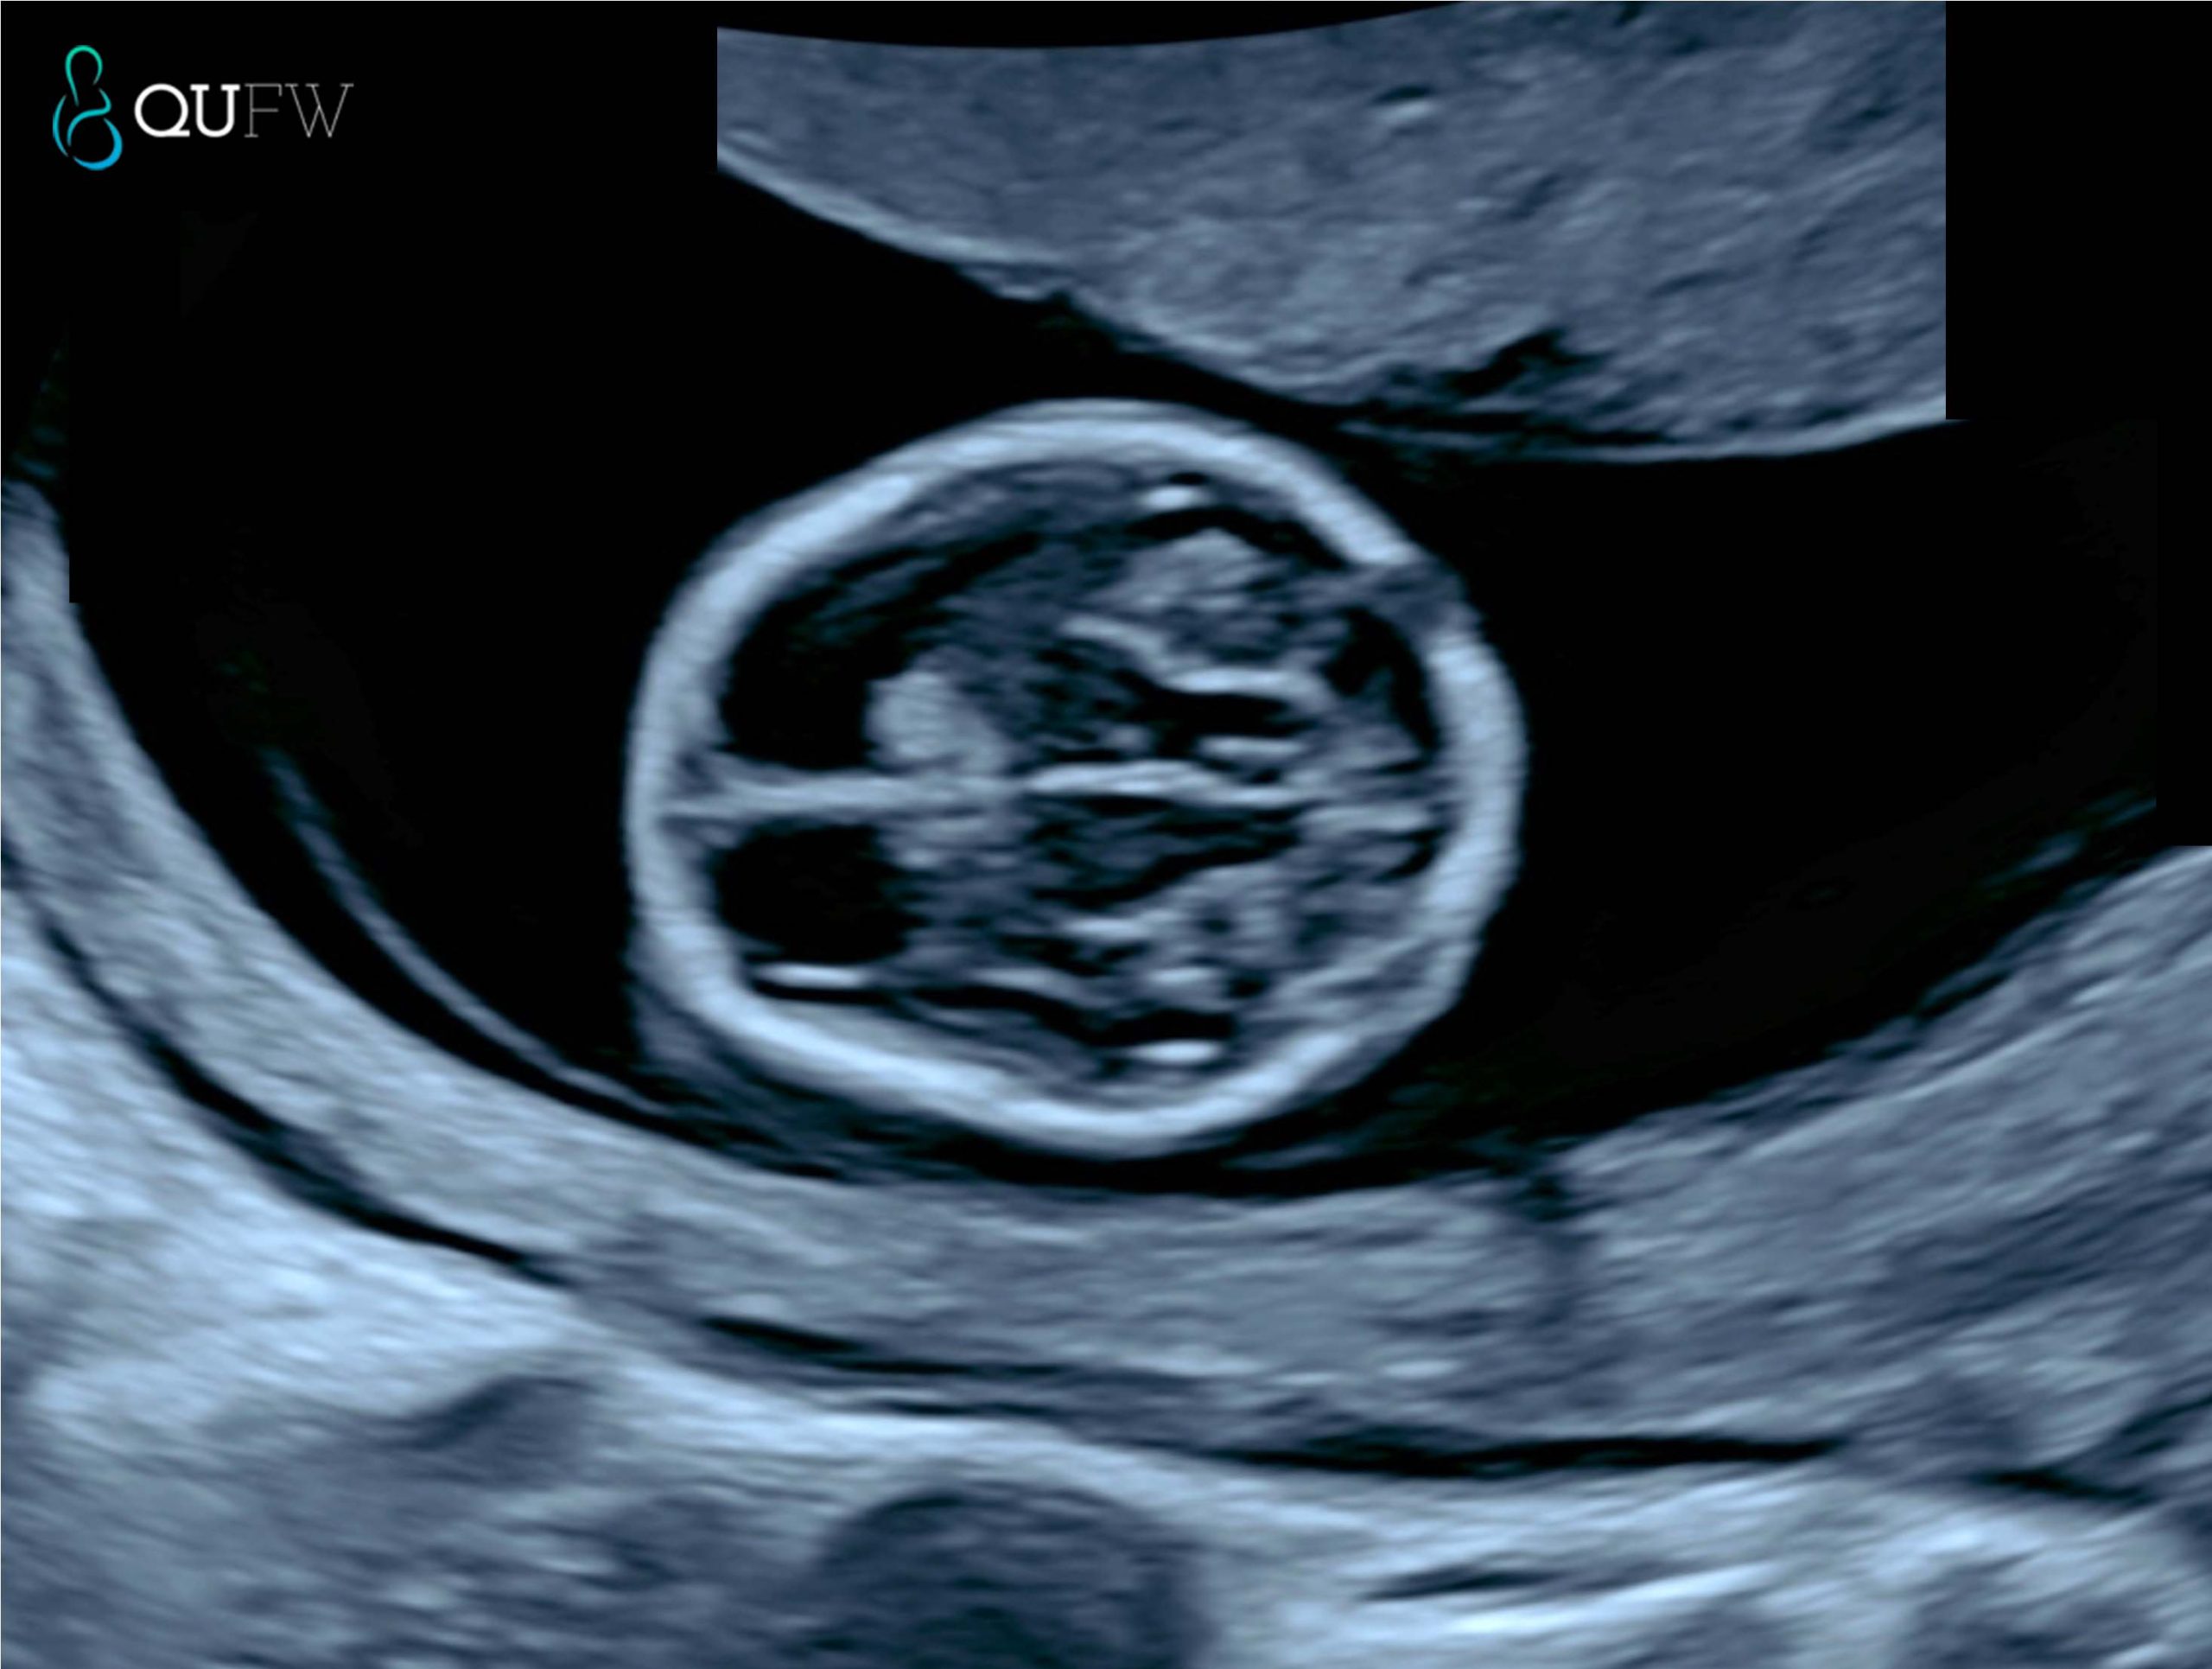

Early structural assessment of the fetal brain

Nuchal translucency assessment